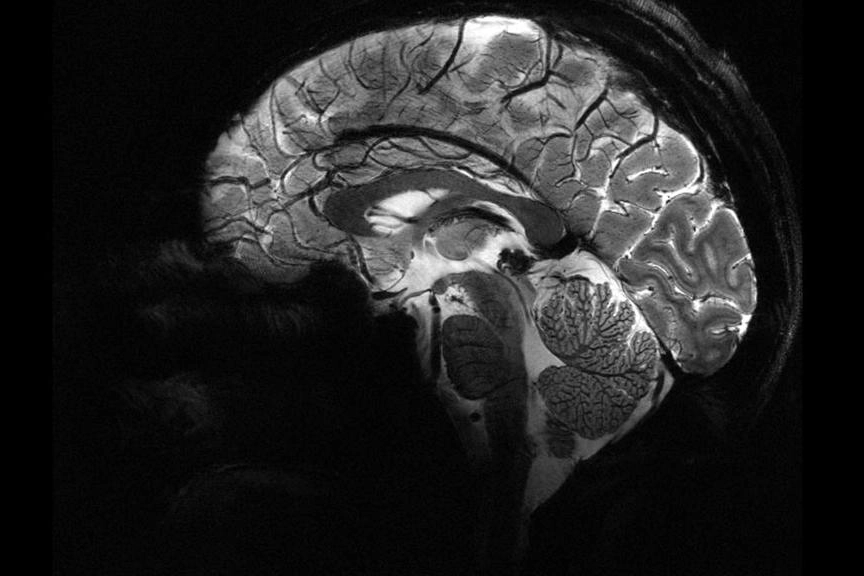

Nottingham Üniversitesi’nden bilim insanları, UK Biobank’ta yer alan 15 binden fazla yetişkinin verileriyle sağlıklı beyin yaşlanmasını tanıyan bir yapay zekâ modeli geliştirdi. Model, pandemiden önce tarananlarla, önce ve pandemi sırasında taranan iki grubun beyin yaşlarını karşılaştırdı.

Science Alert'in haberine göre, Araştırmaya göre, pandemi sürecinde insan beyninin yaşlanma hızı ortalama 5,5 ay öne çekildi.

Çalışmayı yürüten nörolog Ali-Reza Mohammadi-Nejad, “COVID geçirmeyenlerde bile belirgin artış gördük. İzolasyon ve belirsizlik gibi faktörler beyin sağlığını etkiledi” dedi.